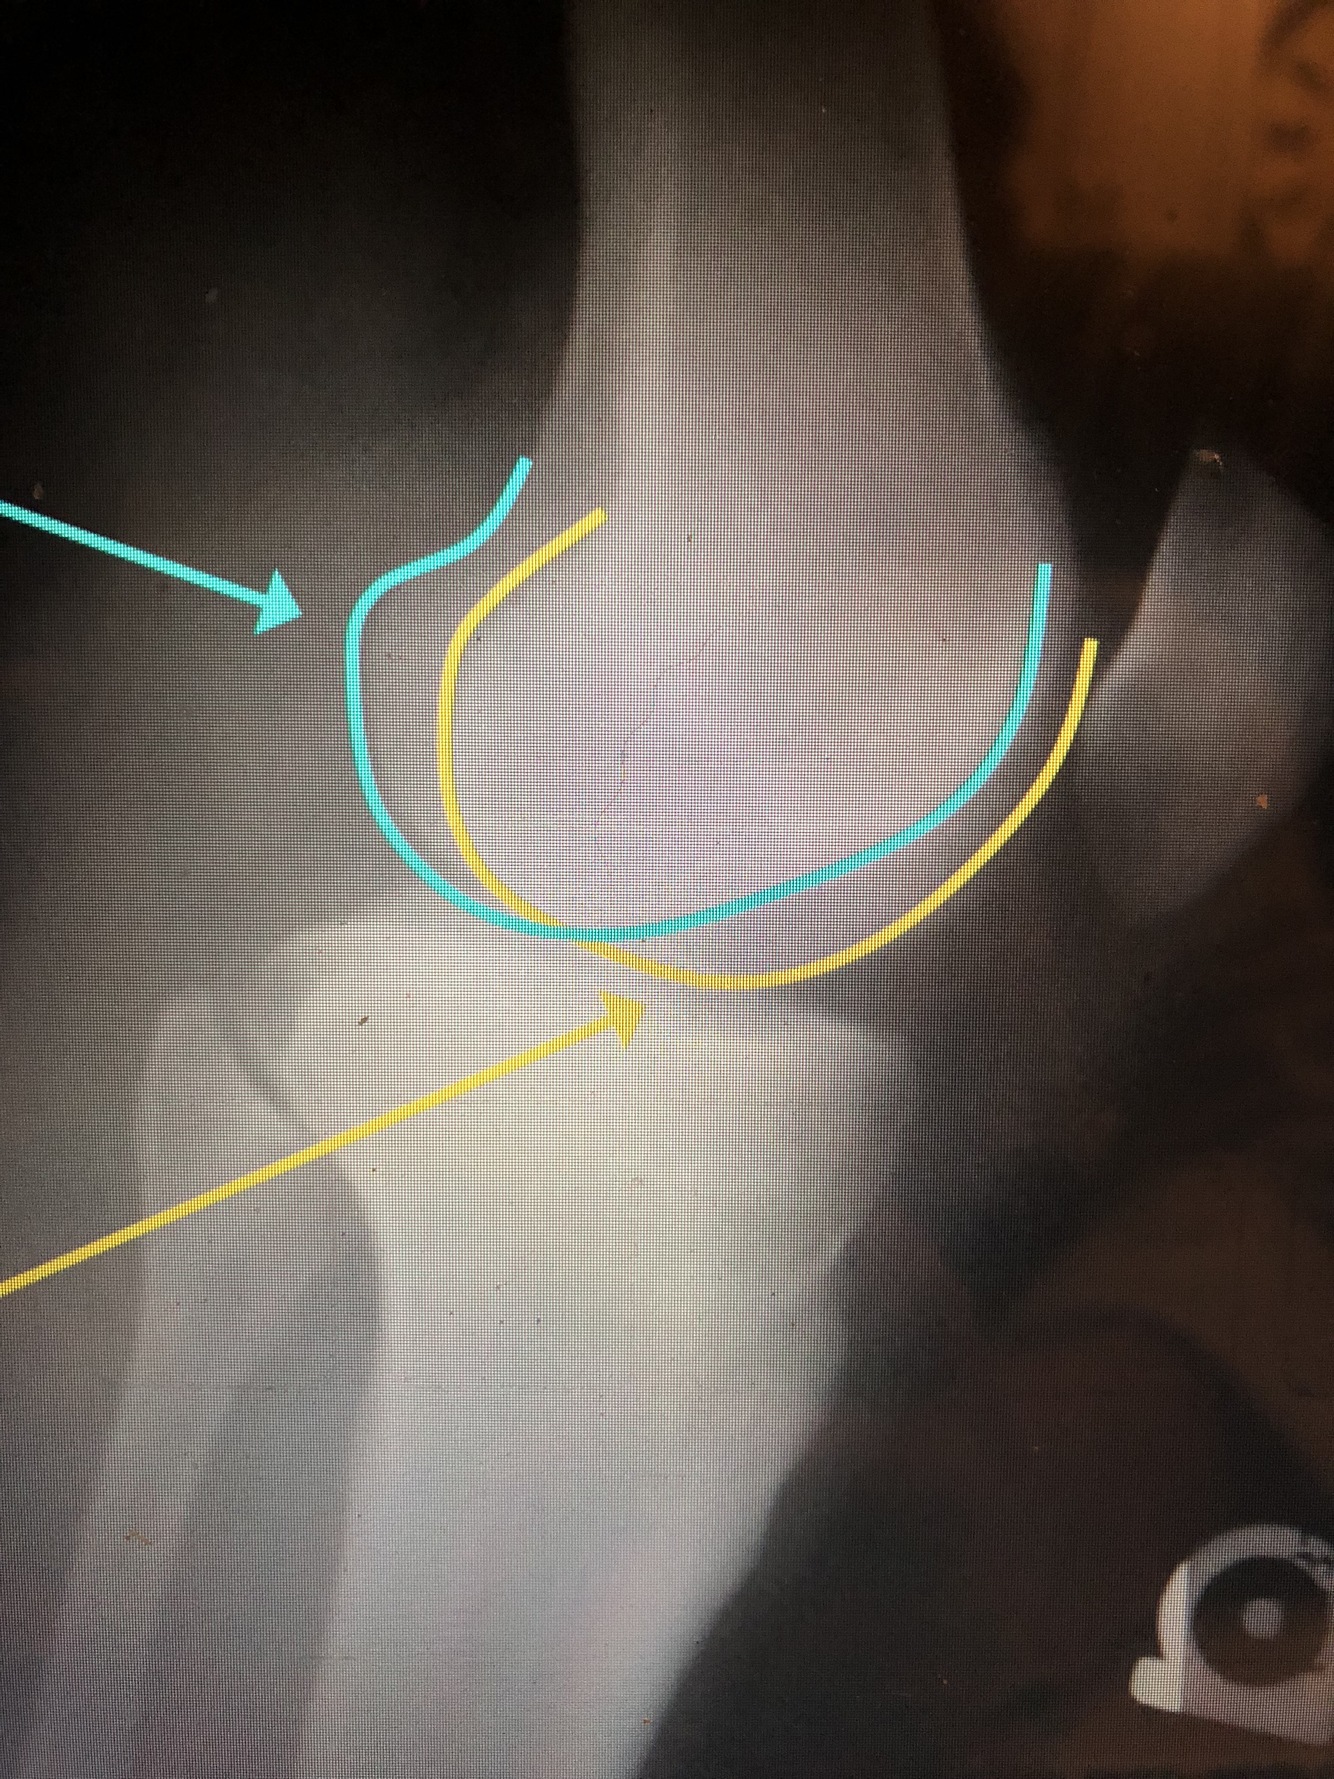

What is the light blue line?

Lateral Femoral Condyle

•Usually projects more proximally and is smaller

What is the yellow line?

Medial Femoral Condyle

•Usually is larger and is projected more distally

In lateral knee, which femoral condyle is more distal and larger?

medial